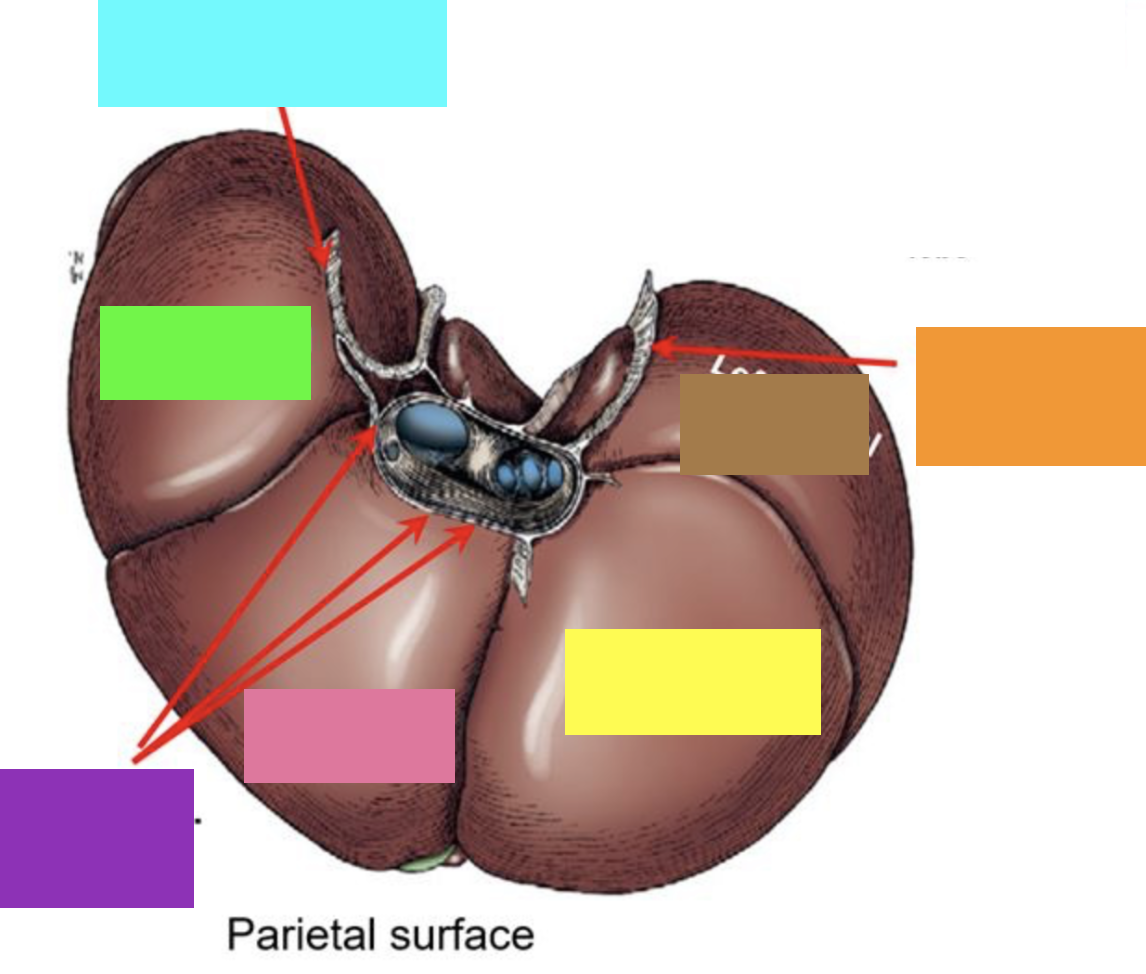

blue box

right triangular ligament

green box

right lateral lobe

purple box

coronary ligament

pink box

right medial lobe

yellow box

left medial lobe

orange box

left triangular ligament

brown box

left lateral lobe